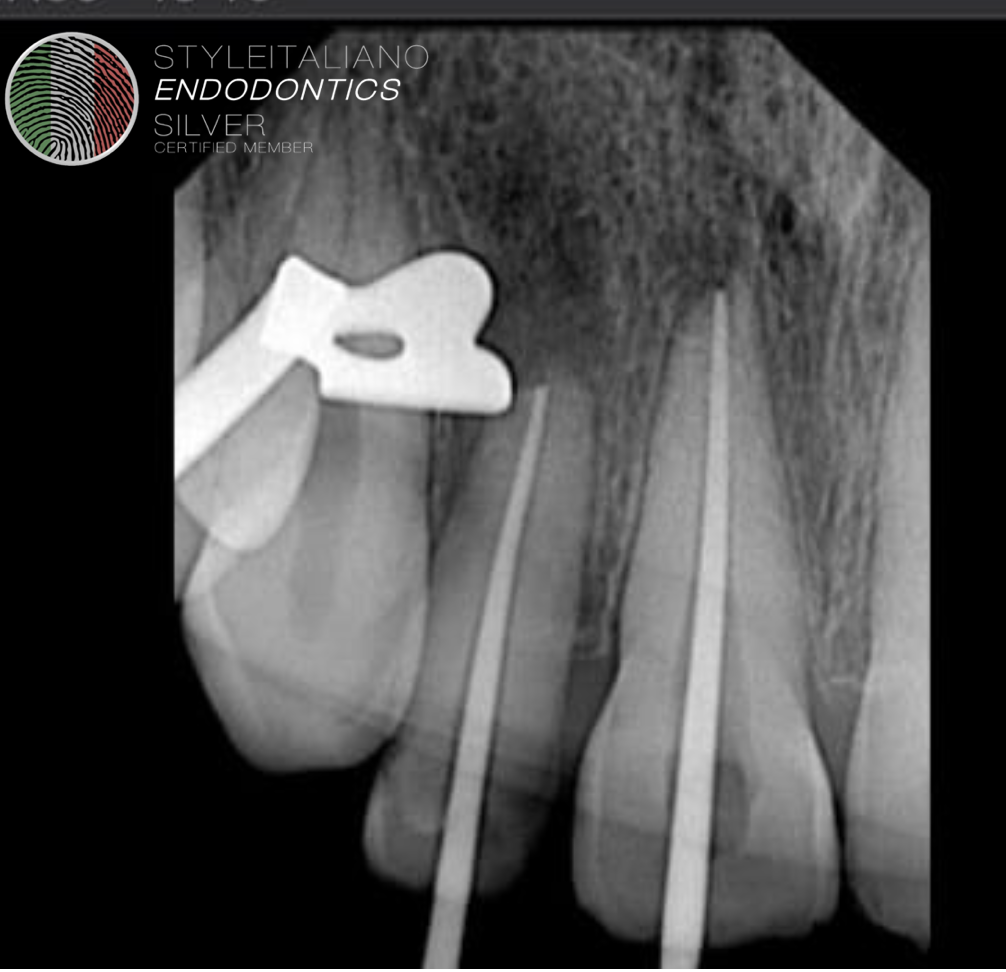

Fig. 2

Tooth was carefully extruded with the help of luxators and forceps about 4mm inside the socket. And splinted with the help of wire.